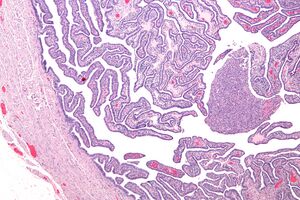

Micrograph of salpingitis – a component of pelvic inflammatory disease. H&E stain.

Upon a pelvic examination, cervical motion, uterine, or adnexal tenderness will be experienced.[5] Mucopurulent cervicitis and or urethritis may be observed. In severe cases more testing may be required such as laparoscopy, intra-abdominal bacteria sampling and culturing, or tissue biopsy.[15][23]

Definitive criteria include histopathologic evidence of endometritis, thickened filled Fallopian tubes, or laparoscopic findings. Gram stain/smear becomes definitive in the identification of rare, atypical and possibly more serious organisms.[24] Two thirds of patients with laparoscopic evidence of previous PID were not aware they had PID, but even asymptomatic PID can cause serious harm.